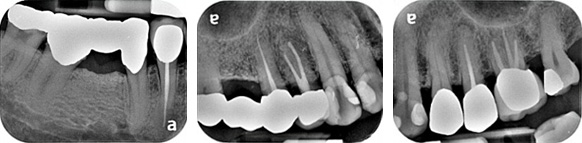

X-rays

- Interproximal calculus: 17M, 15D, 25MD, 26D, 33M, 37M, 47D, 48M

- Generalized mild horizontal bone loss

- Widening of PDL space: 35M/D

- 1:1 crown to root ratio: 26

- Apical radiolucency: 25

- Short root filling: 25